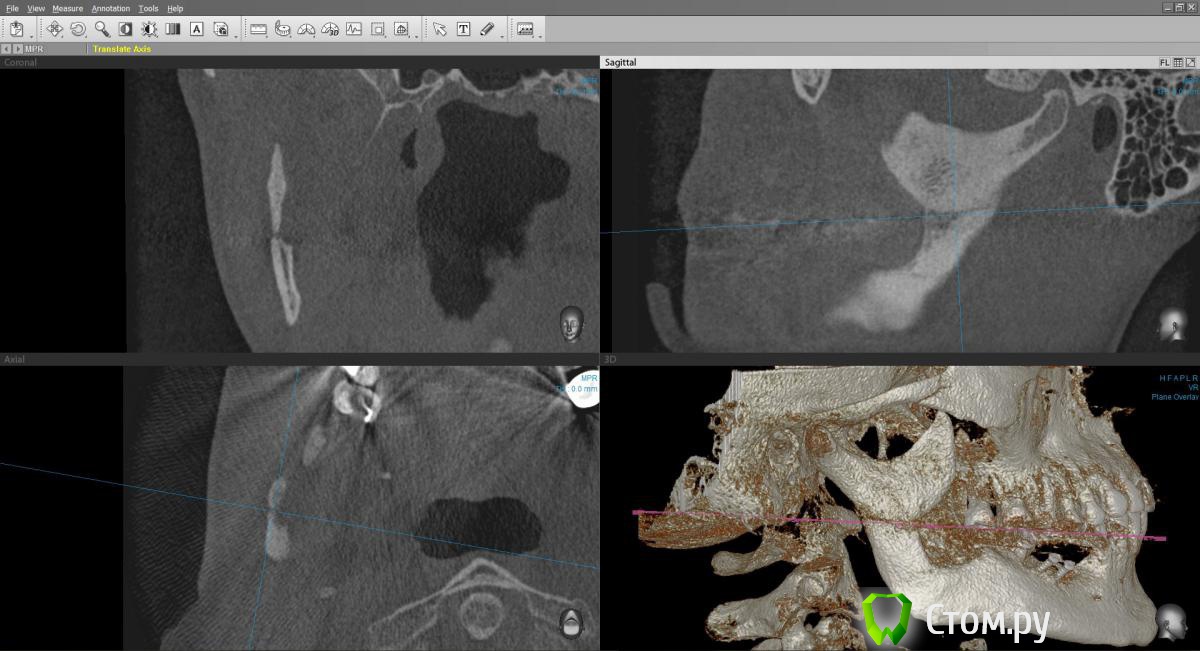

Марьяна Опубликовано 22 ноября, 2014 Автор Поделиться Опубликовано 22 ноября, 2014 Попробую. В программе конечно проще поймать линии переломов.Ну вот ..в области конкретно ветви: Ссылка на комментарий

Марьяна Опубликовано 22 ноября, 2014 Автор Поделиться Опубликовано 22 ноября, 2014 В области угла зигзагообразная линия ..практически уже не визуализируется: Ссылка на комментарий